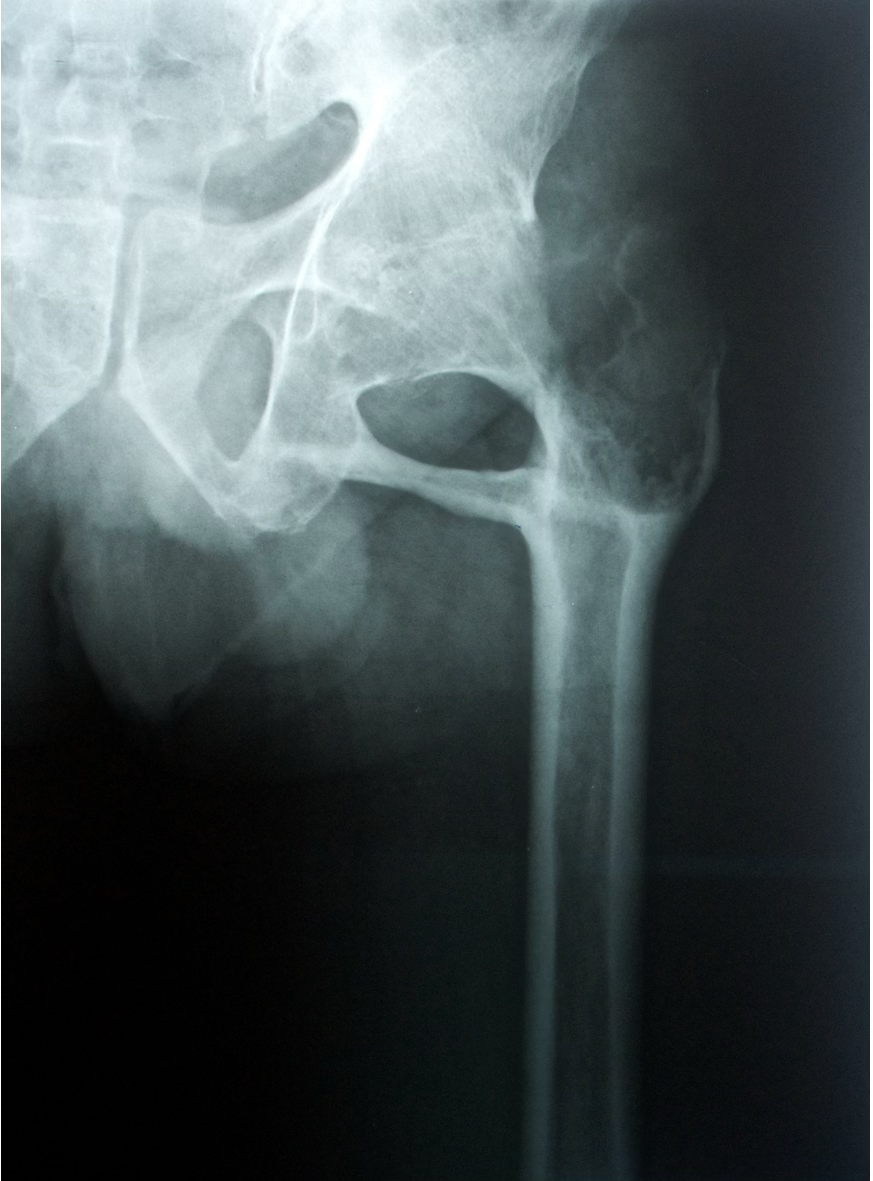

X Ray findings-LOSS

The classic radiographic features of OA are:

• Loss of joint space.

• Osteophyte formation.

• Subchondral sclerosis.

• Subchondral cysts.

Any classification you know?

The Kellgren-Lawrence (KL) Classification is a grading system used to assess the severity of osteoarthritis.

Kellgren-Lawrence Grading System for Osteoarthritis

Grade 1 (Doubtful OA)

- Doudtful osteophytosis.

Grade 2 (Mild OA)

- Definite osteophytosis.

Grade 3 (Moderate OA)

- Definite JSN.

Grade 4 (Severe OA)

- Deformity.